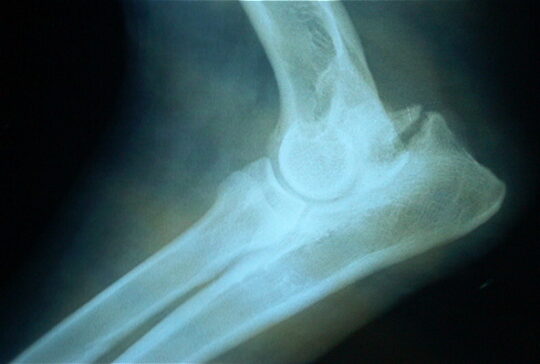

El diagnóstico de la espondilosis deformante se realiza a través de una combinación de historia clínica, examen físico y pruebas de imagen. El médico evaluará los síntomas del paciente, como dolor de cuello o espalda, rigidez, debilidad en los brazos o las piernas, y dificultad para caminar o mantener el equilibrio. El examen físico puede incluir pruebas de fuerza, reflejos y sensibilidad. El médico también puede solicitar radiografías, resonancia magnética o tomografía computarizada para confirmar el diagnóstico.

El diagnóstico de la espondilosis se realiza a través de radiografías y, en algunos casos, puede ser necesario realizar pruebas adicionales como resonancias magnéticas o tomografías computarizadas para evaluar la extensión de los cambios en la columna vertebral.